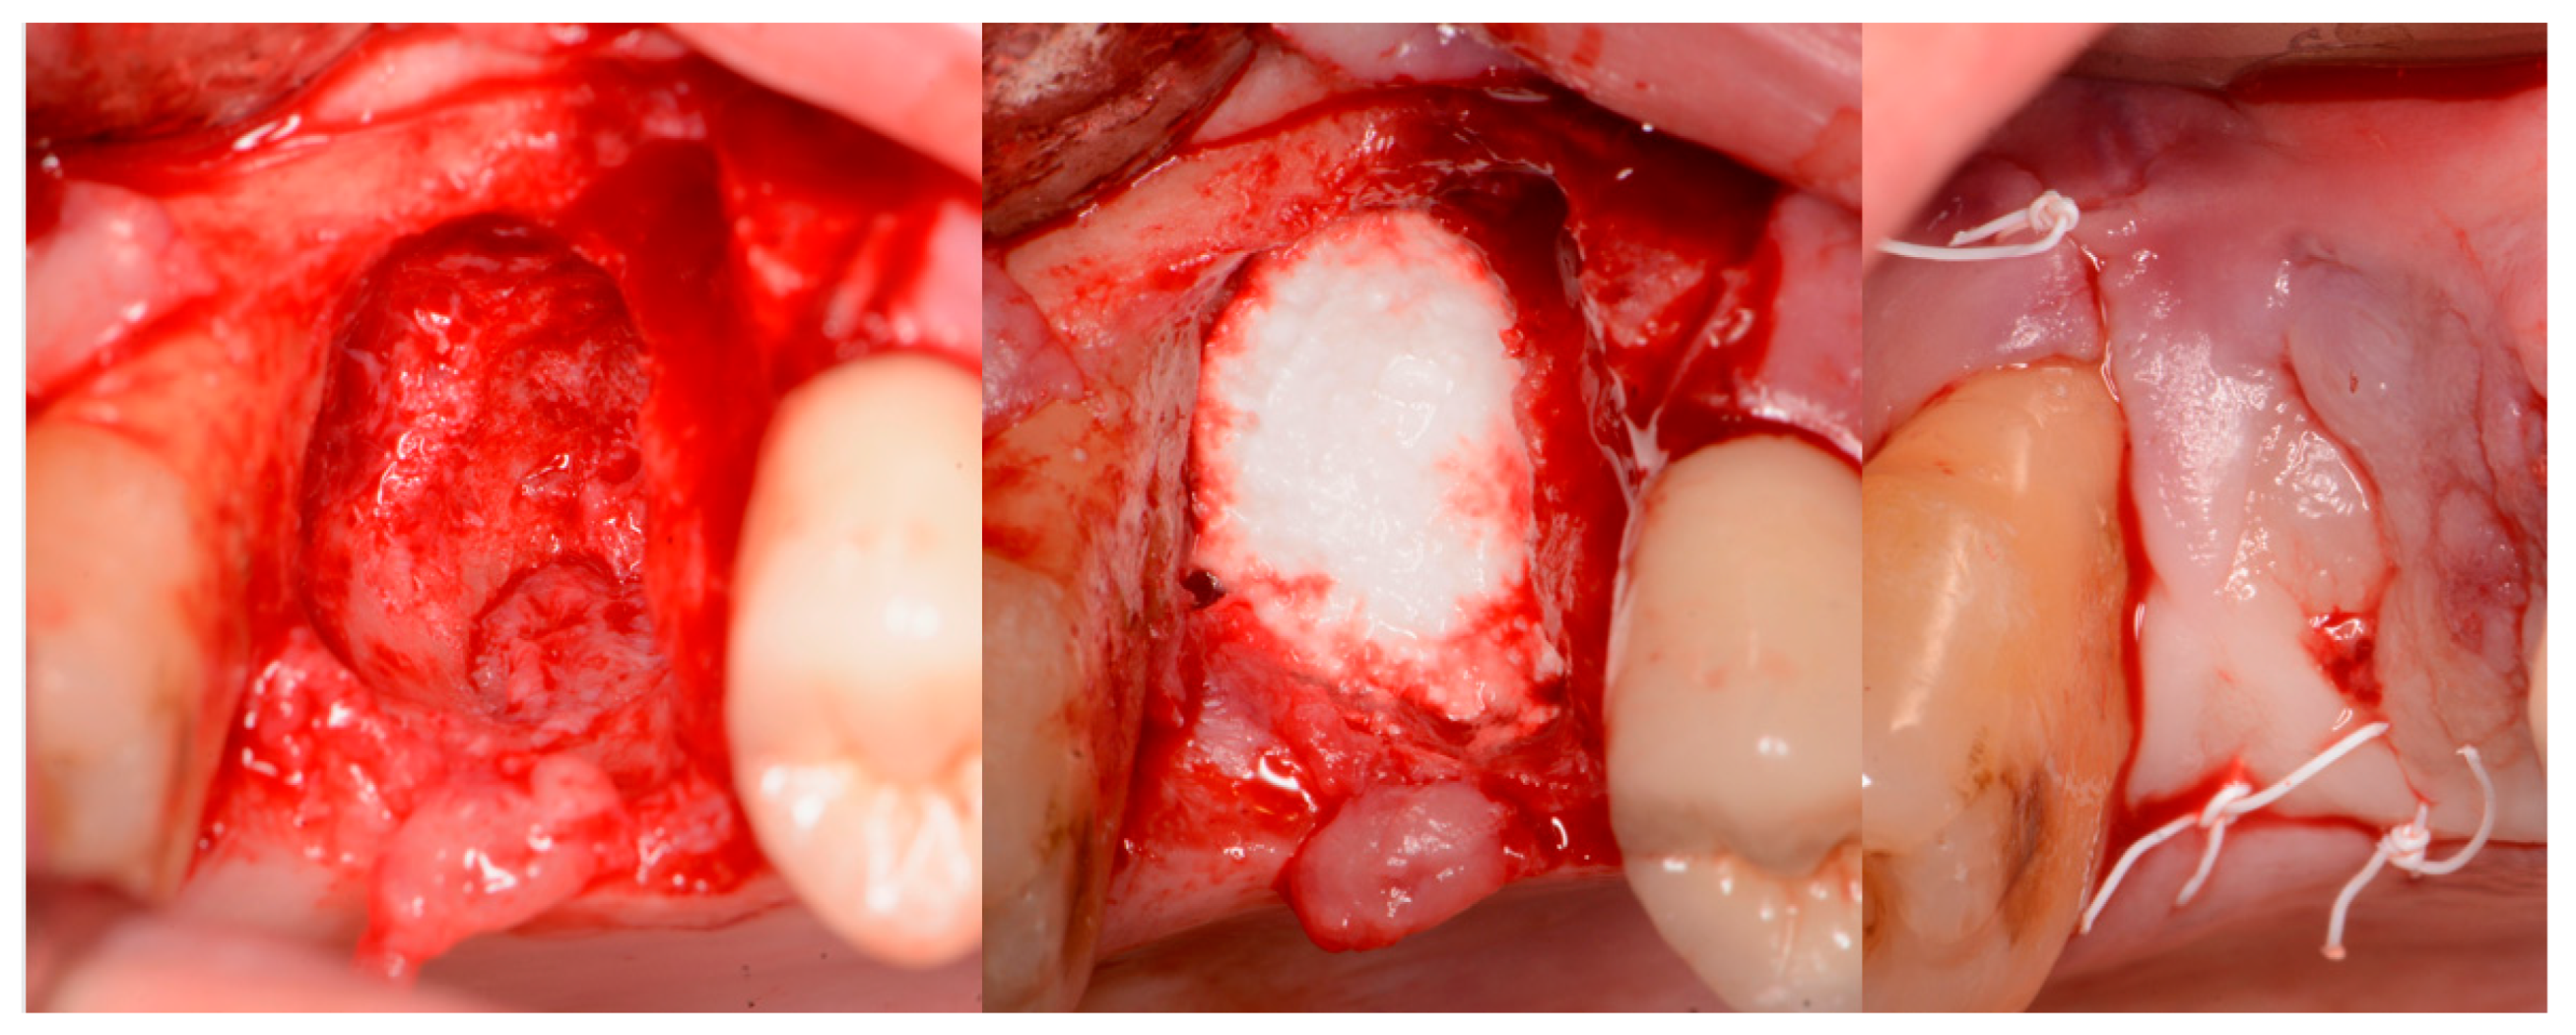

A critical question is about what happens histologically to the graft and at what stage during healing. For example, when delayed socket grafting was performed at a site where a large defect was present following extraction (Figure 18, left), a healing period of 3 weeks post-extraction was needed, allowing primary closure post-graft. This gives us more predictability and simpler surgery, plus two attempts to clean the site. EthOss graft material was placed into the socket (Figure 18, middle) and primary closure with the flap was achieved and secured with sutures (Figure 18, right). Intraoral physical exam and radiographic measurement showed all sites to have regenerated vertically 3–6 mm and horizontally 4–6 mm with new host bone allowing for successful placement of the implants. A core sample was obtained from one case to confirm the series to be in line with earlier findings. Histology was performed by core biopsy at 10 weeks following graft placement and demonstrated well-preserved reactive (woven) trabecular bone with intertrabecular tissue composed of uniformly collagen-rich myofibroblastic tissue and 60% of the core consisting of bone (Figure 19).

Figure 18.

Delayed socket grafting with flap exposure of the site (left), placement of EthOss graft to fill the defect (middle) and flap placement to achieve primary closure (right).